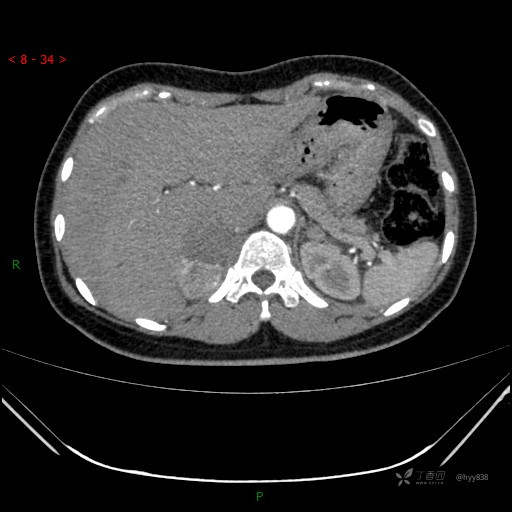

动脉期